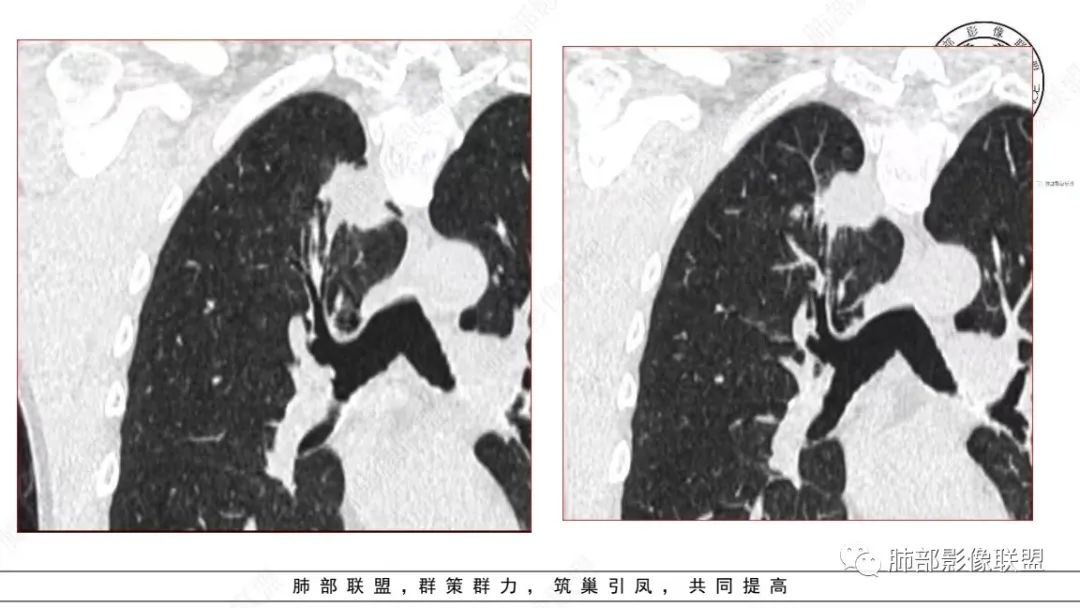

衡妈:中年男性,右肺上叶尖段不规则实性病灶,边缘多深分叶局部形似并见数条长毛刺,与胸膜面数条牵拉中年男性,右肺上叶尖段不规则实性病灶,边缘多深分叶局部形似枫叶,侧胸膜局部幕状增厚,病灶增强后不均匀中等强化。考虑恶性肿瘤,腺癌可能,鉴别炎性肉芽肿(结核)、炎性肌纤维母细胞瘤。

谢加平:右肺上叶尖段内侧胸膜下分叶状结节,不规则,见尖角状凸起,边缘支气管锥形中断,实性不均匀强化,血管进入增粗和集血管束特点,宽基底胸膜牵拉,形成兔耳征,冠状面结节外侧见指头状凸起,恶性特点明显,支持浸润性腺Ca。

影像诊断

本研究对22处BA的CT影像进行分析,发现以下方面对诊断本病有一定提示意义:①病变部位:本组病例均为周围型病变,多位于下叶,且以胸膜下区为主,与既往研究结果一致。本病细支气管黏膜上皮的起源赋予了其特有的位置分布。②类型:本组GGO14处,实性结节8处。Chang等收集的14处BA中,GGO6处、实性结节8处,与既往研究结果基本一致。此外,部分学者报道呈空洞表现的BA。由此可见,BA的影像表现多样,但主要表现为GGO和实性结节。③大小:本研究显示BA普遍较小,最大径约(0.9±0.7)cm,95%的病变不超过2.0cm。王蓓等、高何等分别纳入8例、15例BA,病灶平均最大径均为1.0cm,与本研究结果一致。④形态:本组BA无论表现为GGO还是实性结节,其形态不规则且边缘毛糙,仅少部分体积较小的BA可呈类圆形或椭圆形,与Kamata等的研究结果相似,推测BA的形态学改变与肿瘤无包膜有关。⑤伴发征象:本研究中BA多伴有中央或外周空泡征、细支气管充气征及血管征,其中以中央空泡征最具特征。刘芳兵等报道2例表现为GGO的BA均伴空泡征;苏雷等报道11例BA中,伴有空泡征8例、血管征10例。可见空泡征和血管征对诊断本病具有重要意义。上述征象与镜下瘤内、瘤周常见细支气管及伴行的厚壁血管有关。此外,胸膜牵拉征、分叶征及毛刺征罕见。⑥强化方式:实性结节表现的BA增强扫描呈延迟性显著强化,部分病灶动脉期可见血管造影征,血管走行自然,未见破坏。血管造影征与镜下病变常见细支气管动脉束穿行相符,此征象也反映了肿瘤位于细支气管周围的定位。⑦随访中病灶保持稳定或缓慢增长。此段内容及病例图片摘自并感谢,黄勇教授、王越老师-细支气管腺瘤的CT表现,发表于中国医学影像杂志。